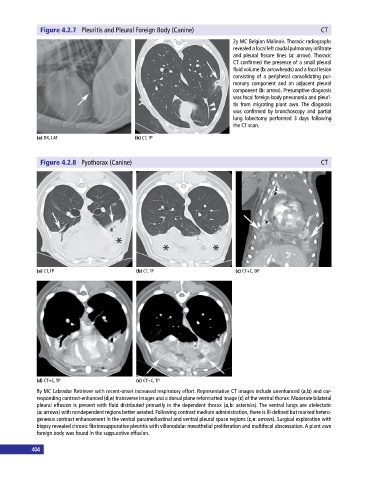

Figure 4.2.7 Pleuritis and Pleural Foreign Body (Canine) CT

2y MC Belgian Malinois. Thoracic radiographs

revealed a focal left caudal pulmonary infiltrate

and pleural fissure lines (a: arrow). Thoracic

CT confirmed the presence of a small pleural

fluid volume (b: arrowheads) and a focal lesion

consisting of a peripheral consolidating pul-

monary component and an adjacent pleural

component (b: arrow). Presumptive diagnosis

was focal foreign‐body pneumonia and pleuri-

tis from migrating plant awn. The diagnosis

was confirmed by bronchoscopy and partial

lung lobectomy performed 3 days following

the CT scan.

Figure 4.2.8 Pyothorax (Canine) CT

8y MC Labrador Retriever with recent‐onset increased respiratory effort. Representative CT images include unenhanced (a,b) and cor-

responding contrast‐enhanced (d,e) transverse images and a dorsal plane reformatted image (c) of the ventral thorax. Moderate bilateral

pleural effusion is present with fluid distributed primarily in the dependent thorax (a,b: asterisks). The ventral lungs are atelectatic

(a: arrows) with nondependent regions better aerated. Following contrast medium administration, there is ill‐defined but marked hetero-

geneous contrast enhancement in the ventral paramediastinal and ventral pleural space regions (c,e: arrows). Surgical exploration with

biopsy revealed chronic fibrinosuppurative pleuritis with villonodular mesothelial proliferation and multifocal abscessation. A plant awn

foreign body was found in the suppurative effusion.